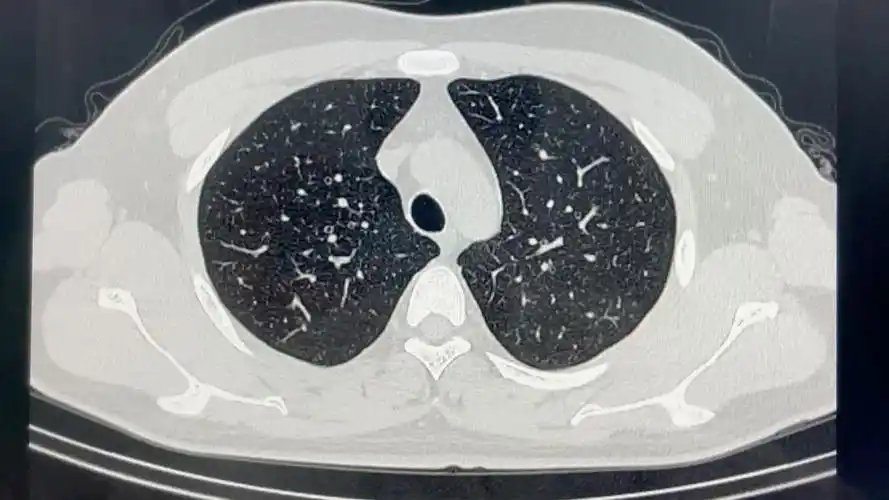

正常胸部ct的肺窗影像